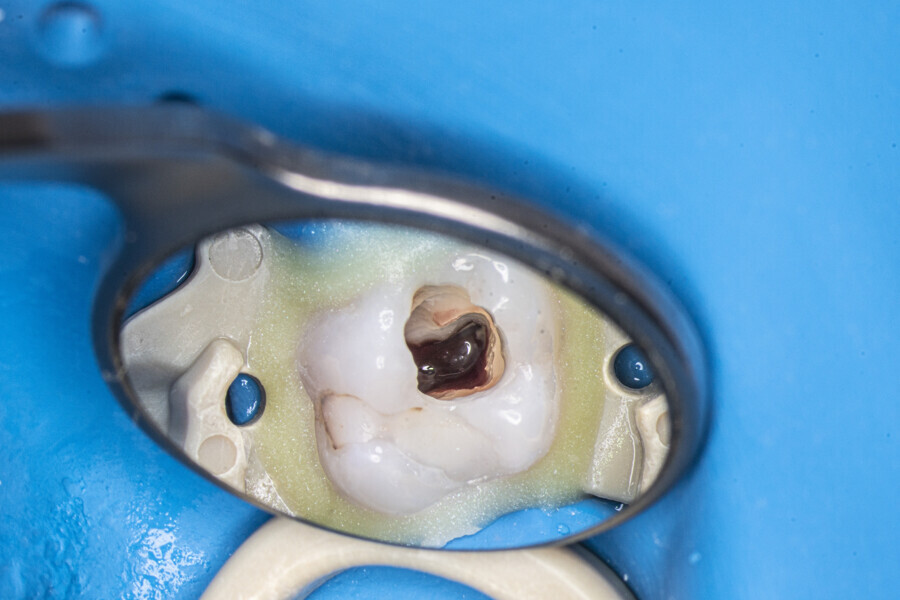

The first trials of the LPE concept were performed on extracted human molars. Although the dynamics of fluid during root canal irrigation are completely different in vivo than in extracted teeth, these kinds of trials provide initial information about the procedure. Some of these teeth had apices closed with a coat of wax and composite resin to close the apical delta and simulate the periapical tissue. After creation of the access cavity, the pulp chamber was cleaned with continuous irrigation with 5.25% NaClO activated with a SkyPulse laser (Fotona) in AutoSWEEPS mode (20 Hz, 15 mJ). A 25/0.07 reciprocating file (Shenzhen Perfect Medical Instruments) was used to perform the pre-flaring procedure. After opening the coronal third, continuous irrigation with 5.25% NaClO activated with the laser was used to clear the debris for 30 seconds. After removing the debris, a #10 C-PILOT file (VDW) was used to establish apical patency, without forcing the file if possible. In some cases, apical patency was reached already at this stage of root canal preparation. In all cases, the second step of instrumentation was the preparation of the middle third with the same file, and the same irrigation procedure was performed. Subsequently, the C-PILOT file was used to reach the apical foramen. At this stage, apical patency was reached in most cases, but in some roots, there was no possibility of entering the apical foramen. The working length was confirmed with a radiograph with the hand file. Usually, the next procedure to be done is apical preparation, but the LPE concept is based on an enhanced irrigation protocol. Following this protocol, irrigation was performed for 5 minutes with continuous flow of 5.25% NaClO activated with the SkyPulse laser in AutoSWEEPS mode (20 Hz, 20 mJ) with a conical sapphire fibre. The next step was alternating irrigation with 17% EDTA for 30 seconds, with 5.25% NaClO for 30 seconds and with 17% EDTA for 30 seconds, all activated with AutoSWEEPS, followed by irrigation for another 5 minutes with 5.25% NaClO activated with AutoSWEEPS. In most cases, the next step after this stage of enhanced irrigation was the calibration of the apical constriction rather than apical preparation per se, but this step requires further investigation.

At the first appointment, both teeth were opened, the old restorations were removed, all the root canal orifices were located and the first mesiobuccal (MB1), distobuccal (DB) and palatal canals were shaped. In both teeth, the MB2 orifices were located, but the canals were not shaped. The preparation phase was similar to that explained earlier. During the root canal preparation phase, the hand file was used to establish patency after each reciprocating instrument, and the canals were flushed with NaClO activated with the SkyPulse laser in SWEEPS mode for 10–15 seconds. After reaching two-thirds of the estimated working length with the reciprocating files, the LPE enhanced irrigation protocol with the SkyPulse laser was employed. The apical preparation was not performed at this stage. Owing to a lack of time at this appointment, the canals were flushed with EDTA and sterile water, and a 2% solution of chlorhexidine was poured as an intra-canal dressing. Both teeth were closed with temporary composite restorations.

At the second appointment, the temporary restorations were removed, and the chlorhexidine was washed out with sterile water and EDTA. After opening the orifice of the MB2 canal in the first molar, the operator was not able to reach patency in the canal. Therefore, the isthmus between the MB1 and MB2 orifices was opened with diamond-coated ultrasonic tips. Finally, patency was reached. Shaping the MB2 canal in the second molar was possible only to the place of the junction with the MB1 canal. The CBCT imaging had revealed previously that the MB2 canal should have its own lumen in the apical third, but the place of the junction was below the curvature. The possibility of locating this space without damaging the root was very poor. At this stage, the LPE enhanced irrigation protocol was performed again. After performing of the irrigation protocol, the apical preparation was performed for all the canals. The final irrigation protocol was performed with 5 minutes of constant flow of 5.25% NaClO for 2 minutes, alternating with 17% EDTA for 30 seconds, with 5.25% NaClO for 30 seconds and 17% EDTA for 30 seconds, and irrigation with 5.25% NaClO for 5 minutes. All the irrigants were activated with an EDDY sonic tip (VDW). After performing the periapical radiographs, a CBCT scan was performed to confirm the separate path of the sealer that filled previously unprepared spaces of the MB2 canals in both teeth. In both cases, it was clearly visible on the CBCT image that all the previously unprepared spaces were filled with the obturation material.